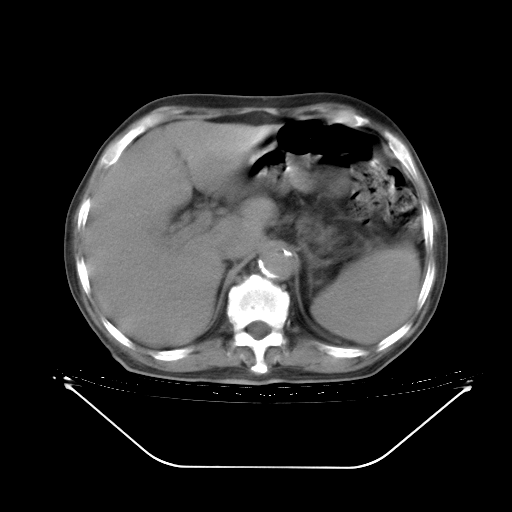

今天复查肺部CT,发现双肺广泛磨玻璃样改变。所以我把3月19日和5月9日相隔50天的肺部CT上传。请大家会诊。

5月9日肺部CT(在4月27日齐鲁医院肺部CT描述部分肺组织磨玻璃样改变,12天后肺组织广泛磨玻璃样改变)

2009年5月9日肺部CT